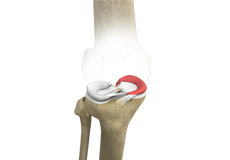

Articular Cartilage and Menisci of the Knee

Movement of the bones causes friction between the articulating surfaces. To reduce this friction, all articulating surfaces involved in the movement are covered with a white, shiny, slippery layer called articular cartilage. The articulating surface of the femoral condyles, tibial plateaus and the back of the patella are covered with this cartilage. The cartilage provides a smooth surface that facilitates easy movement.

To further reduce friction between the articulating surfaces of the bones, the knee joint is lined by a synovial membrane that produces a thick clear fluid called synovial fluid. This fluid lubricates and nourishes the cartilage and bones inside the joint capsule.

Within the knee joint, between the femur and tibia, are two C-shaped cartilaginous structures called menisci. Menisci function to provide stability to the knee by spreading the weight of the upper body across the whole surface of the tibial plateau. The menisci help in load-bearing i.e. it prevents the weight from concentrating onto a small area, which could damage the articular cartilage. The menisci also act as a cushion between the femur and tibia by absorbing the shock produced by activities such as walking, running and jumping.